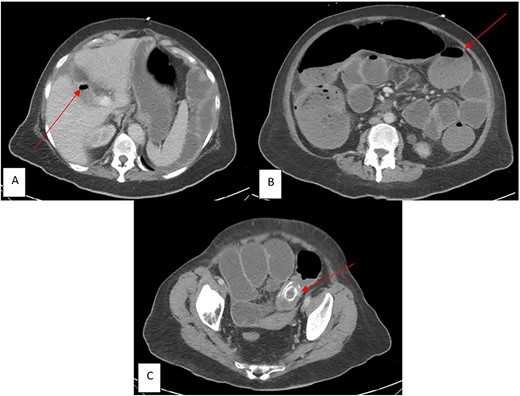

A 69-year-old Caucasian female presented to our institution with a chief complaint of abdominal pain with accompanying nausea, vomiting and constipation for ⁓1 week. Patient was noted to have multiple co-morbidities: chronic obstructive pulmonary disease (COPD), heart failure with reduced ejection fraction (HFrEF), and a recent middle cerebral artery (MCA) ischemic stroke. Vitals were significant for body temperature of 36.7°C, blood pressure was 91/56 mmHg, and pulse rate was 104 beats/min. On a physical exam, the patient displayed tenderness to palpation in the left lower quadrant of her abdomen with abdominal distention and tympany to percussion. Laboratory studies significant for leukocytosis [white blood cell count (WBC) 16.2 u/L] and electrolyte abnormalities (Potassium 3.0 mEq/L, Chloride 102 mEq/L). CT revealed pneumobilia (Fig. 1A), multiple distended loops of bowel consistent with obstruction (Fig. 1B), and a 3.6 × 2.1 cm, high-density structure within the lumen of the distal sigmoid colon indicating impacted gallstone (Fig. 1C). Based on these clinical findings, the patient was diagnosed with sigmoid GI. Considering the risk of perforation and patient’s hemodynamic instability, an emergent laparotomy was performed.

CT imaging in the emergency department (ED) with components of Rigler’s Triad (marked by red arrows): (A) Pneumobilia, (B) distended loops of bowel consist with large bowel obstruction, (C) gallstone impacted in the sigmoid colon.

This case highlights how a case of sigmoid GI induced obstruction can be successfully managed with a simple surgical intervention. Our patient had the classic presentation of being an elderly female with multiple comorbid conditions and cardinal symptoms of bowel obstruction. Due to coinciding hemodynamic instability, identifying components of Rigler’s triad via CT (Fig. 1A–C) was paramount in prompt diagnosis and decision-making to take emergently for intervention. As stated, there was thought of addressing both stone removal and fistula closure but as the patient was requiring higher vasopressor support, a decision was made to forego fistula closure. This appeared to be the most beneficial route as the patient’s recovery and hospitalization was brief and uncomplicated with no indication of recurrence on outpatient follow-up. Our case gives credence to the simple procedure being an adequate intervention for patients that present in severe shock, offering a safer procedure that outweighs the risk of GI recurrence.